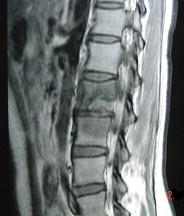

问题 男,33岁,有午后发热,夜间盗汗等,腰部疼痛,活动时加重,休息后减轻,请结合所提供图像,选择最佳答案 ( )

选项 A、骨巨细胞瘤 B、骨髓瘤 C、腰椎骨转移 D、腰椎退行性变 E、腰椎结核

答案 E